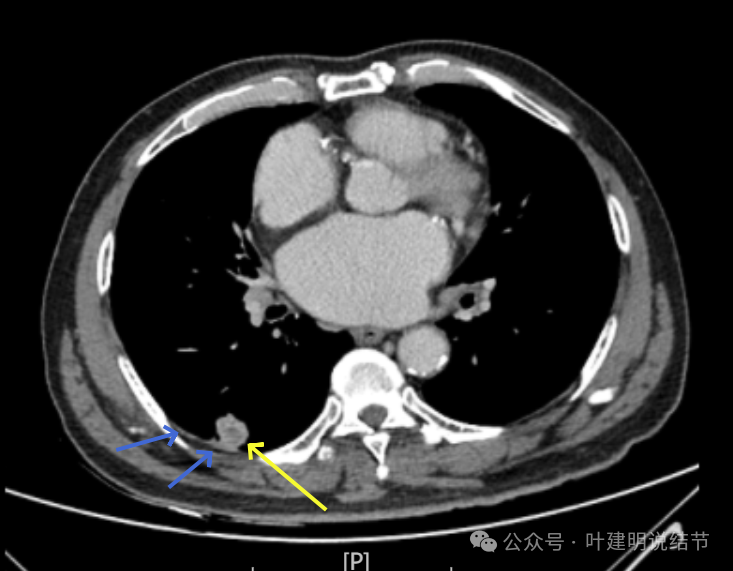

增强纵隔窗见病灶内部的密度好像低于周围区域,像坏死。

邻近胸膜无牵拉,灶内有低密度区,局部有点状液性密度。邻近胸膜较为广泛的增厚或胸膜反应。

病灶与胸膜接触面宽,病灶内部密度较低。